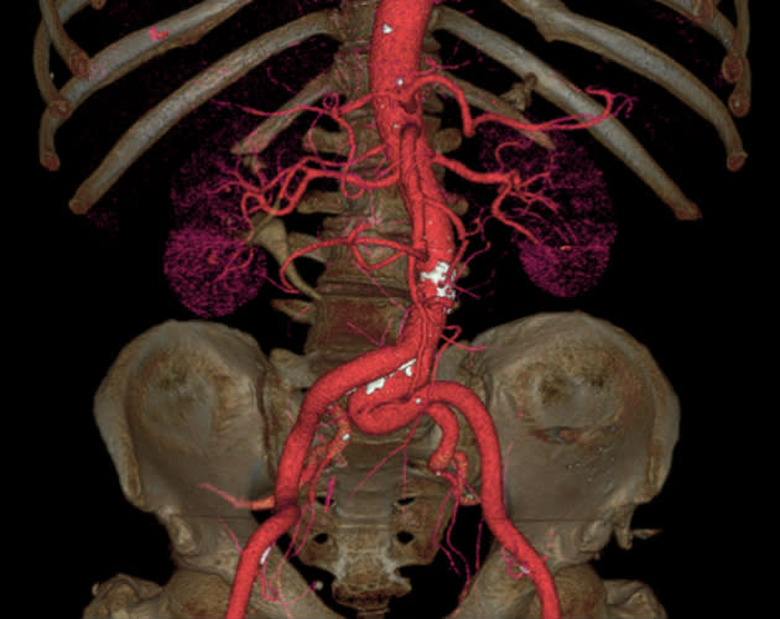

Few people enjoy having a CT scan. In a bleak hospital room, you have to lie flat on your back as a huge circular scanner shoots focused X-rays through your flesh and bones. The entire process can feel a little intimidating, which is why GE Healthcare has come up with the Revolution CT: a whisper-quiet and super-fast scanner that could make medical appointments a little quicker and less stressful for patients. The new machine, which is being trialled by the West Kendall Baptist Hospital in Florida, can capture an entire heart in a single beat, where each rotation takes just 0.28 seconds. That speed, combined with better contrast detection and noise reduction, could also reduce the doses of radiation required in each scan, potentially easing people's fears. In addition, none of these advancements should compromise the quality of the final 3D images — to prove its point, GE Healthcare has released some kinda gross, but undeniably beautiful GIFs of people's innards.

[Image Credit: GE Healthcare]